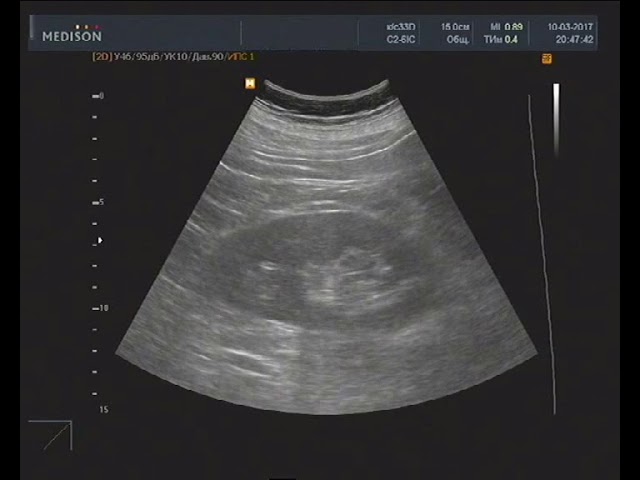

Чем раньше нефросклероз будет диагностирован, тем проще будет нормализовать состояние больного. Однако для постановки правильного диагноза врачам требуются результаты многих анализов, поэтому пациенту придется сдать биохимический анализ крови, мочу, общий анализ крови. Кроме того, специалисты прибегают к таким методам инструментальной диагностики, как ультразвуковое исследование почек, урография и сцинтиграфия почек, радионуклидная рентгенография и проч. Подобные методики позволяют поставить верный диагноз и определить причину, повлиявшую на возникновение нефросклероза.